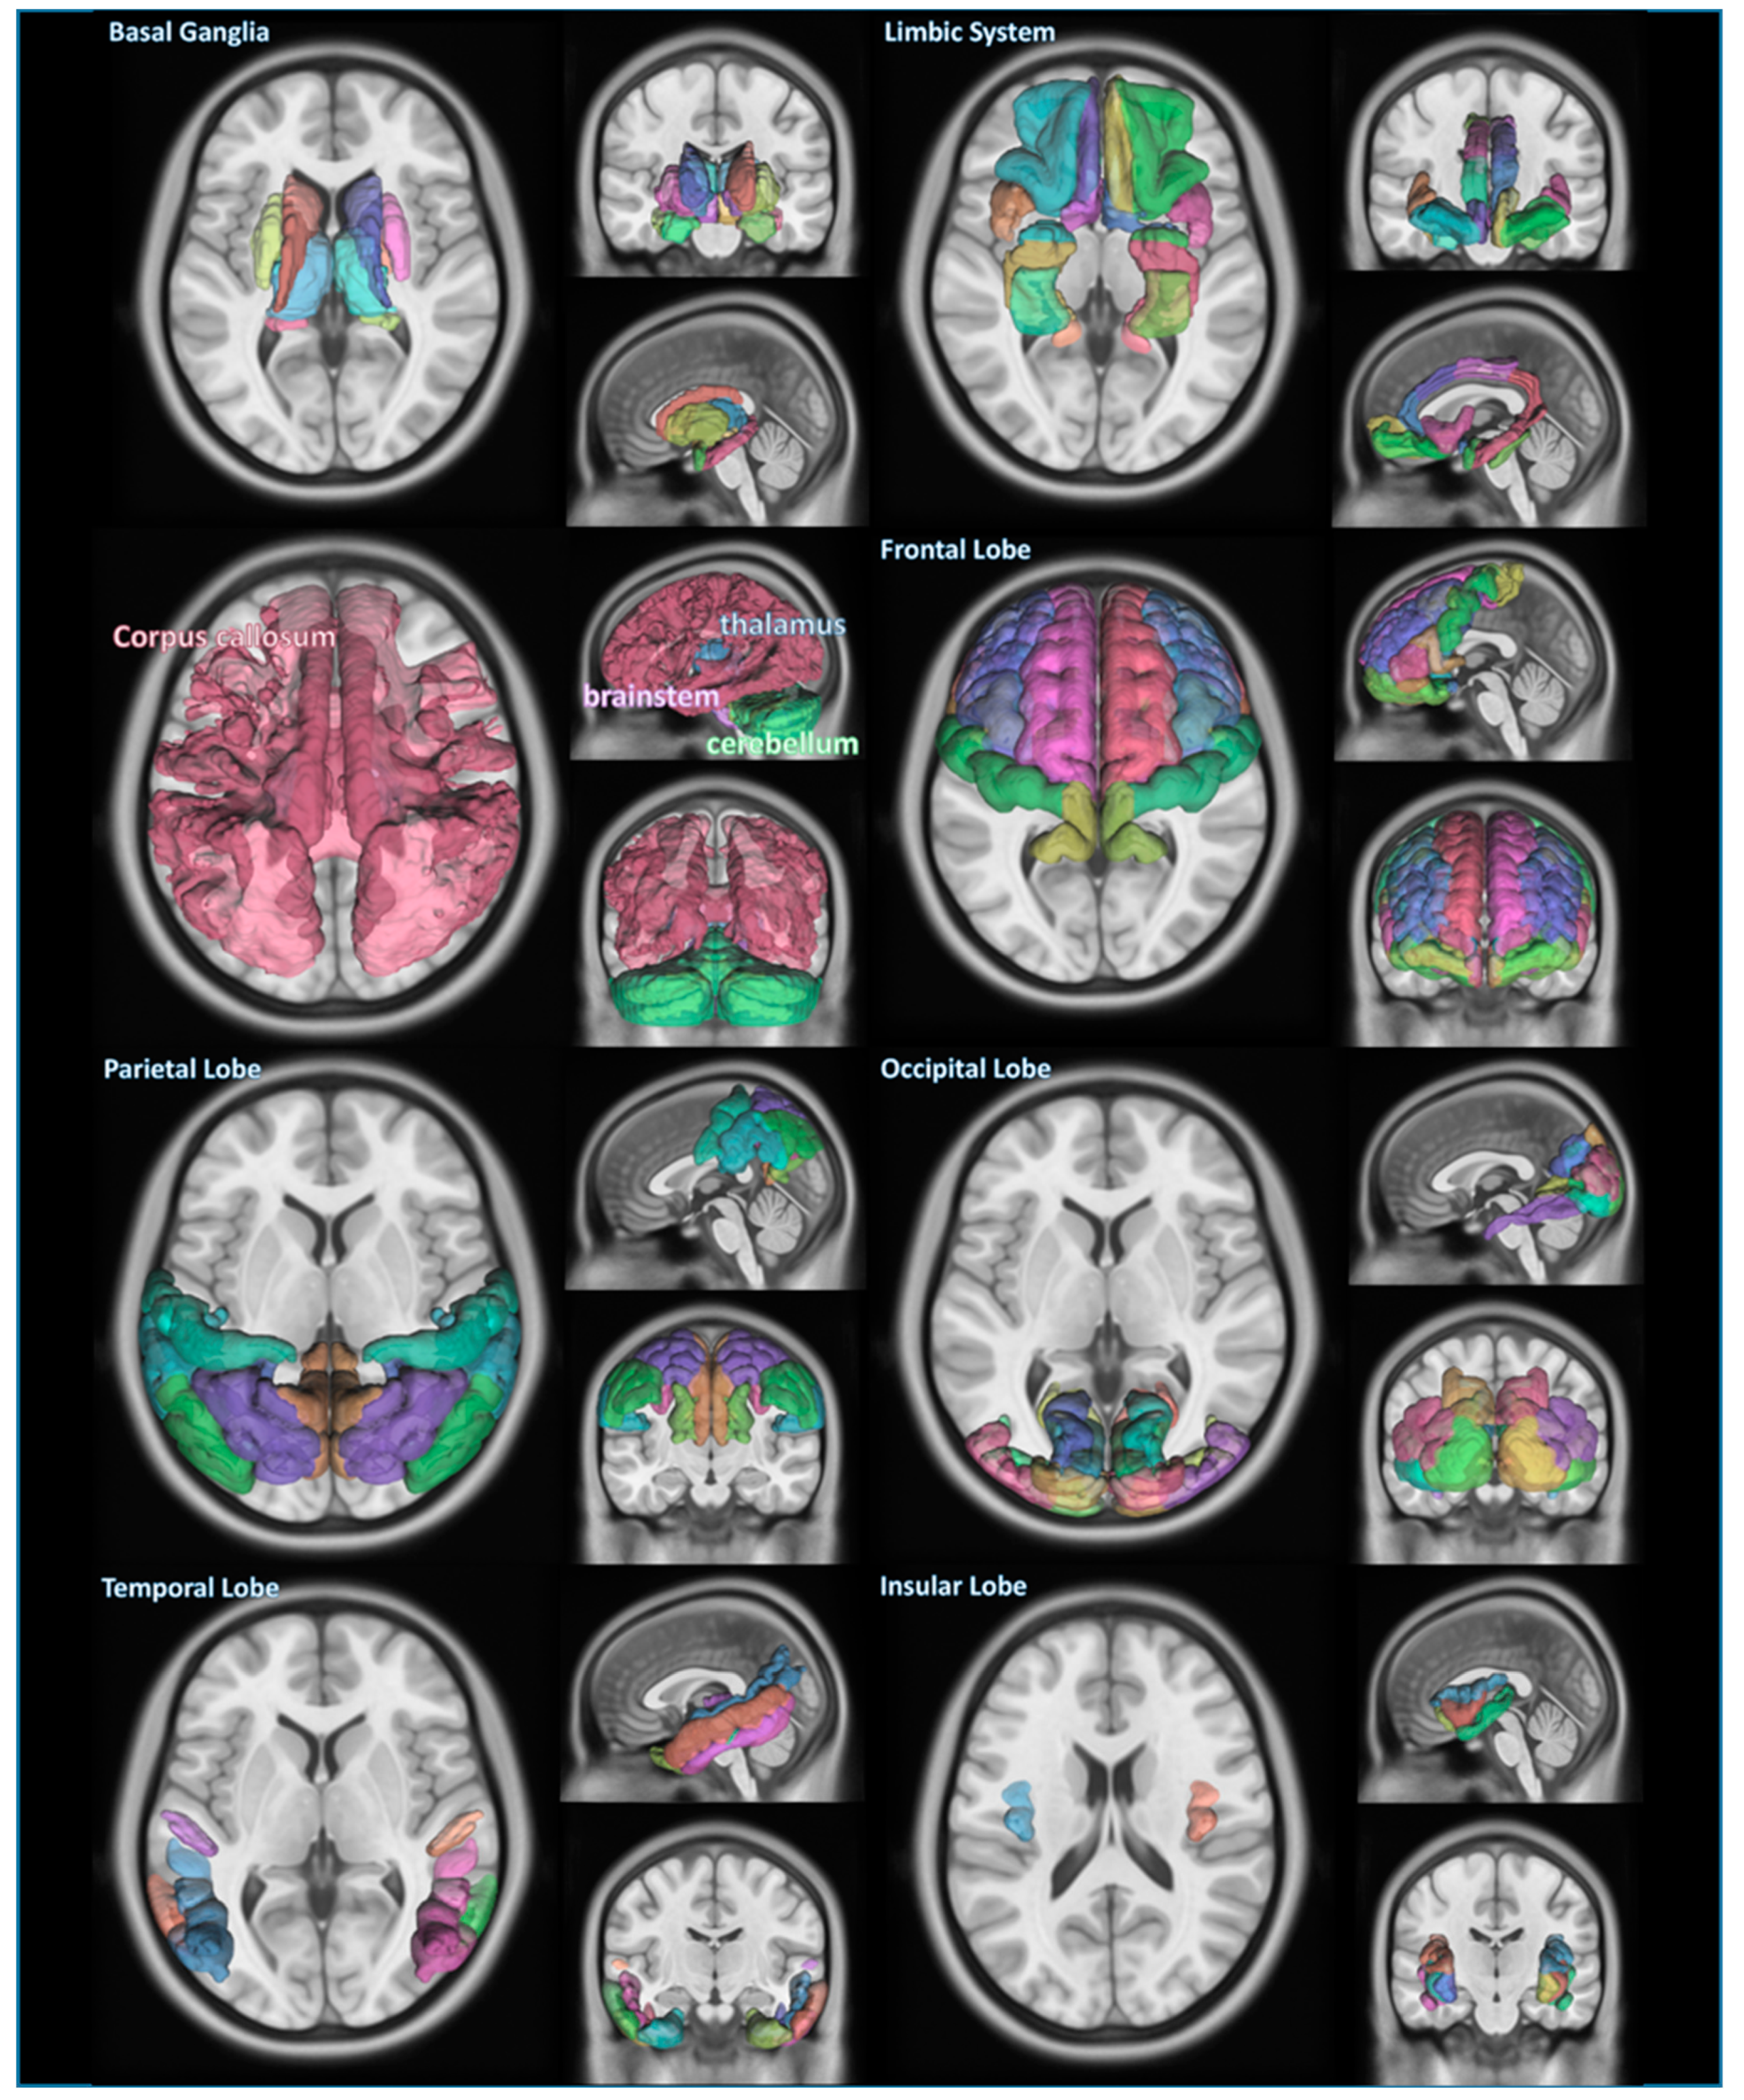

The information regarding the segmented brain regions from the PPMI database was classified by anatomical or functional criteria. Figure 1 shows each classified area of the brain, which is the main subject we investigated.

Figure 1.

Segmentation of several areas of brain in Parkinson’s disease. The areas composed of segmented structures of a PD patient recruited in this study are basal ganglia, limbic system, cerebellum, thalamus, brain stem, corpus callosum, frontal lobe, parietal lobe, occipital lobe, temporal lobe, and insular lobe, which are overlaid on top of MNI templates.